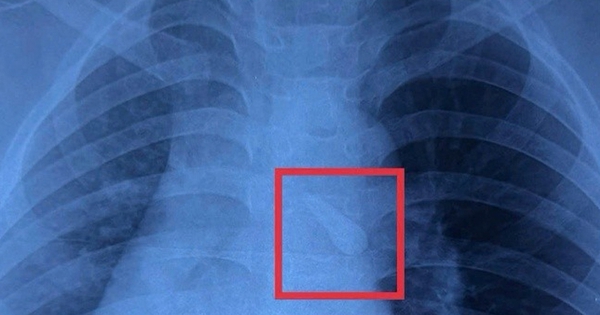

Tai nạn giao thông khiến bé trai 10 tuổi bị gãy răng và hít sặc vào khí quản. Các bác sĩ Bệnh viện Nhi đồng 1 (TP Hồ Chí Minh) đã phẫu thuật nội soi kịp thời, giúp trẻ qua nguy hiểm.